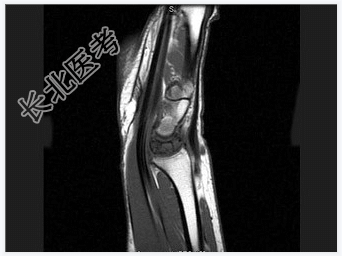

- [材料题] 女,41岁,纺织工,腕部疼痛无力数周。

- 简答题1、结合CR和MR,最可能的诊断是?

- 简答题2、右侧月骨缺血坏死的常见原因是什么?

- 简答题3、右侧月骨缺血坏死的早期症状有哪些?

- 简答题4、右侧月骨缺血坏死的治疗方案有哪些?